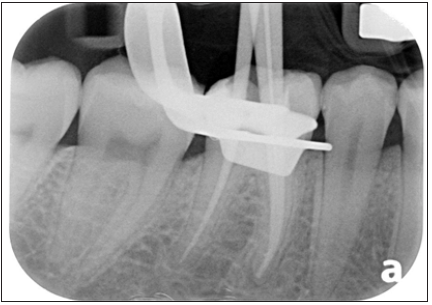

Figure 1:Periapical radiograph inadequate root canal treatment in 46. Periapical radiolucency associated with the mesial roots can be seen. Metallic threaded post can be seen in the distal canal.

In addition to the removal of gutta perchas, final cleaning and shaping of the canal was planned in this visit. If the patient remained comfortable throughout the appointment and if time permits obturation was also planned in the same appointment. Once the removal of gutta perchas were done. Access cavity was explored for presence of cracks and extra canals. No extra canals were found. Endodontic hand files were used to determine working length along with electronic apex locator. The working length was verified with periapical radiograph (Figure 7). The canals were finally cleaned and shaped with Hyflex CM files up to size 25/04. EDTA gel, saline, 2.5% sodium hypochlorite and EDTA liquid were used as irrigants alternatively (Figure 8). Ultrasonic agitation of the irrigates was done with Endoultra from Dentsply. Clinically the fit of the master cones was checked and the verified with a peri apical radiograph at the calculated working length (Figure 9).

Figure 7: Periapical radiograph showing working length determination after gutta percha removal.